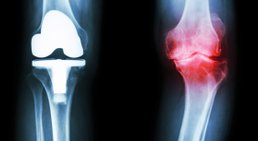

- Kniegelenksersatz bei Arthrose mit Teil- und Totalendoprothesen

Knieprothese

Bei Kniearthrose (Gonarthrose) kommt es zu einem fortschreitenden Gelenkverschleiß, der zu einer Zerstörung des Knorpels im Kniegelenk führt - der Knorpel im...